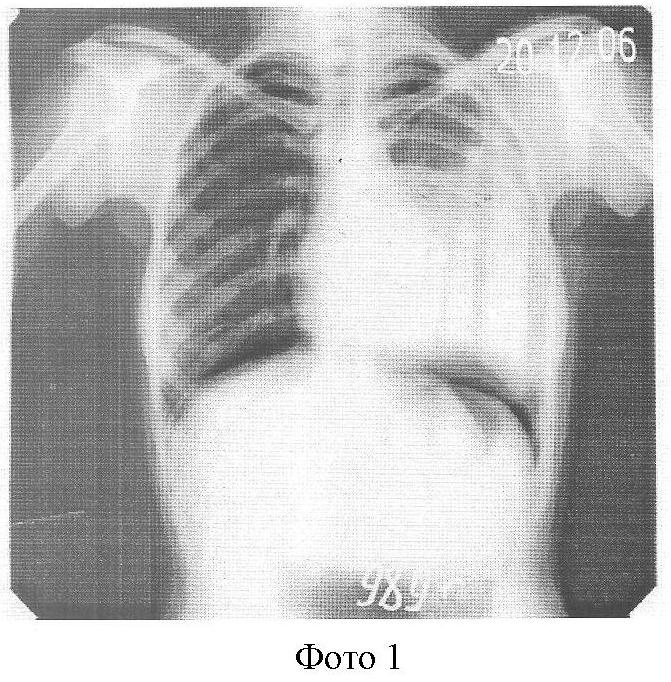

20.12.2006 г. на обзорной R-грамме слева в I-II м/реб. Крупноочаговые тени, от 3-го ребра к низу интенсивное затемнение с косым верхним уровнем – выпот (Фото 1). Синус, купол диафрагмы не дифференцируется.

На фоне противотуберкулезного антибактериального лечения в амбулаторных условиях наложен искусственный пневмоперитонеум, обзорная R-грамма от 20.12.06 г. (Фото 2), где мы наблюдаем приподнятый воздухом купол диафрагмы, который поддерживался в течение 15 мес. За это время жидкость полностью рассосалась без выраженных спаек. Обзорная R-грамма от 30.01.07 г. (Фото 3).